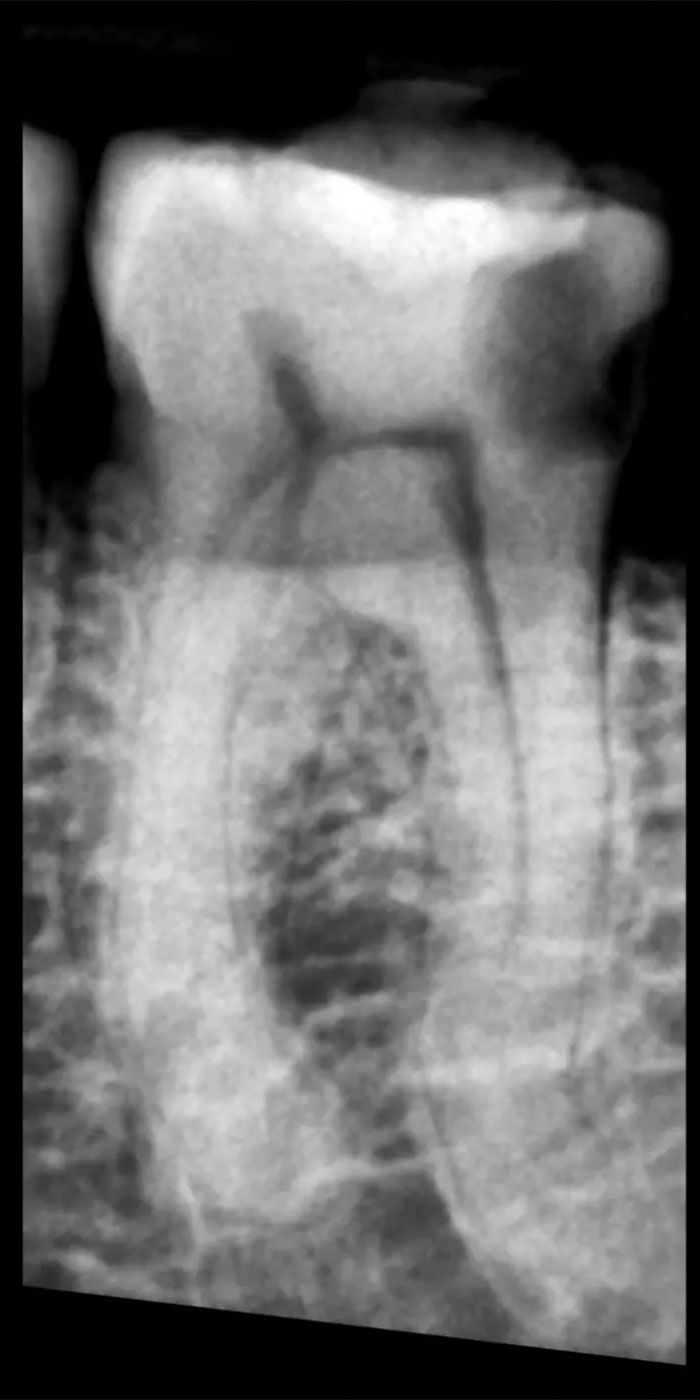

- Our skilled Schenectady root canal dentists will perform a thorough examination and X-rays to assess the extent of damage or infection within the tooth.